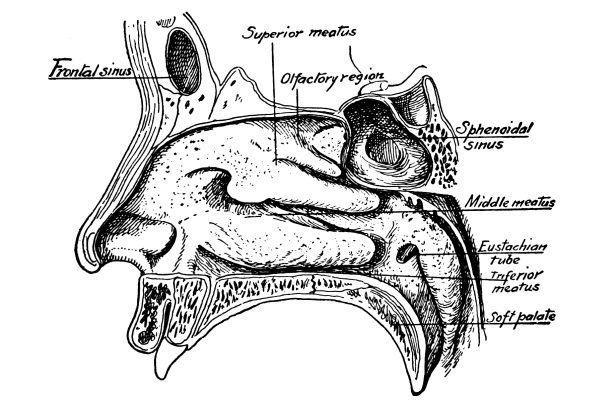

The Ethmoid Bone.—In front of and below the sphenoid and extending forward to the frontal bone is the ethmoid, the last of the cranial bones. It consists of a horizontal cribriform or sieve-like plate, from either side of which depend lateral masses of ethmoid cells. To the inner side of these masses are attached the thin curved turbinated bones, superior and middle, while between them is a vertical plate that forms the bony septum of the nose. Rising from the upper surface of the cribriform plate is another vertical plate, the crista galli, with the olfactory grooves on either side for the reception of the olfactory bulbs, filaments of the olfactory nerve passing down through the perforations of the cribriform plate to the nose. For the brain, which fills almost the entire cavity of the cranium, is supported by the sphenoid and ethmoid bones internally, as it is protected externally by the other cranial bones.

The Cranial Bones, 48—Frontal Bone, 49—Parietal Bones, 49—Occipital Bone, 50—Occipito-frontalis Muscle, 51—Temporal Bones, 51—Sphenoid or Wedge Bone, 52—Ethmoid Bone, 53—Turbinated Bones, 53—Ossification of Sutures, 53—Bones of the Face, 53—Superior Maxillary Bones, 54—Antrum of Highmore, 54—Malar or Cheek Bones, 54—Lachrymal Bones, 54—Palate Bones, 54—Nasal Bones, 55—Vomer, 55—Inferior Turbinated Bones, 55—Inferior Maxillary Bone or Lower Jaw, 55—Sublingual Gland, 56—Submaxillary Gland, 56. |

| The Organs of Special Sense | 57 |

The Nose, 57—The Sense of Smell, 58—The Mouth, 59—The Hyoid Bone, 60—The Teeth, 60—The Sense of Taste, 61—Salivary Glands, 61—The Tonsils, 62—The Ear, 63—Eustachian Tubes, 63—Sensation of Hearing, 65—The Eye, 66—Lachrymal Gland, 68—Coats of the Eye, 68—Light Rays and Sight, 70—Accommodation, 72—Color Perception, 73. |